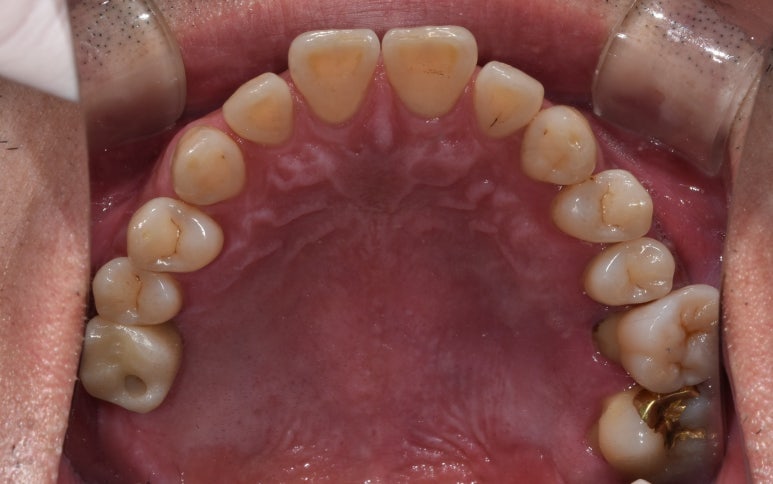

실제 구내 사진을 함께 보실까요?

임플란트 수술 전후

(전) 2022-04-28 (후) 2023-04-06

사진을 보시면 특히 #26 같은 경우는 육안으로 보기에도 치아 뿌리가 노출되는 등

임플란트가 시급한 상태였는데, 치료 후에는 제자리에 치아가 잘 자리잡고 있는 것을 확인할 수 있습니다.